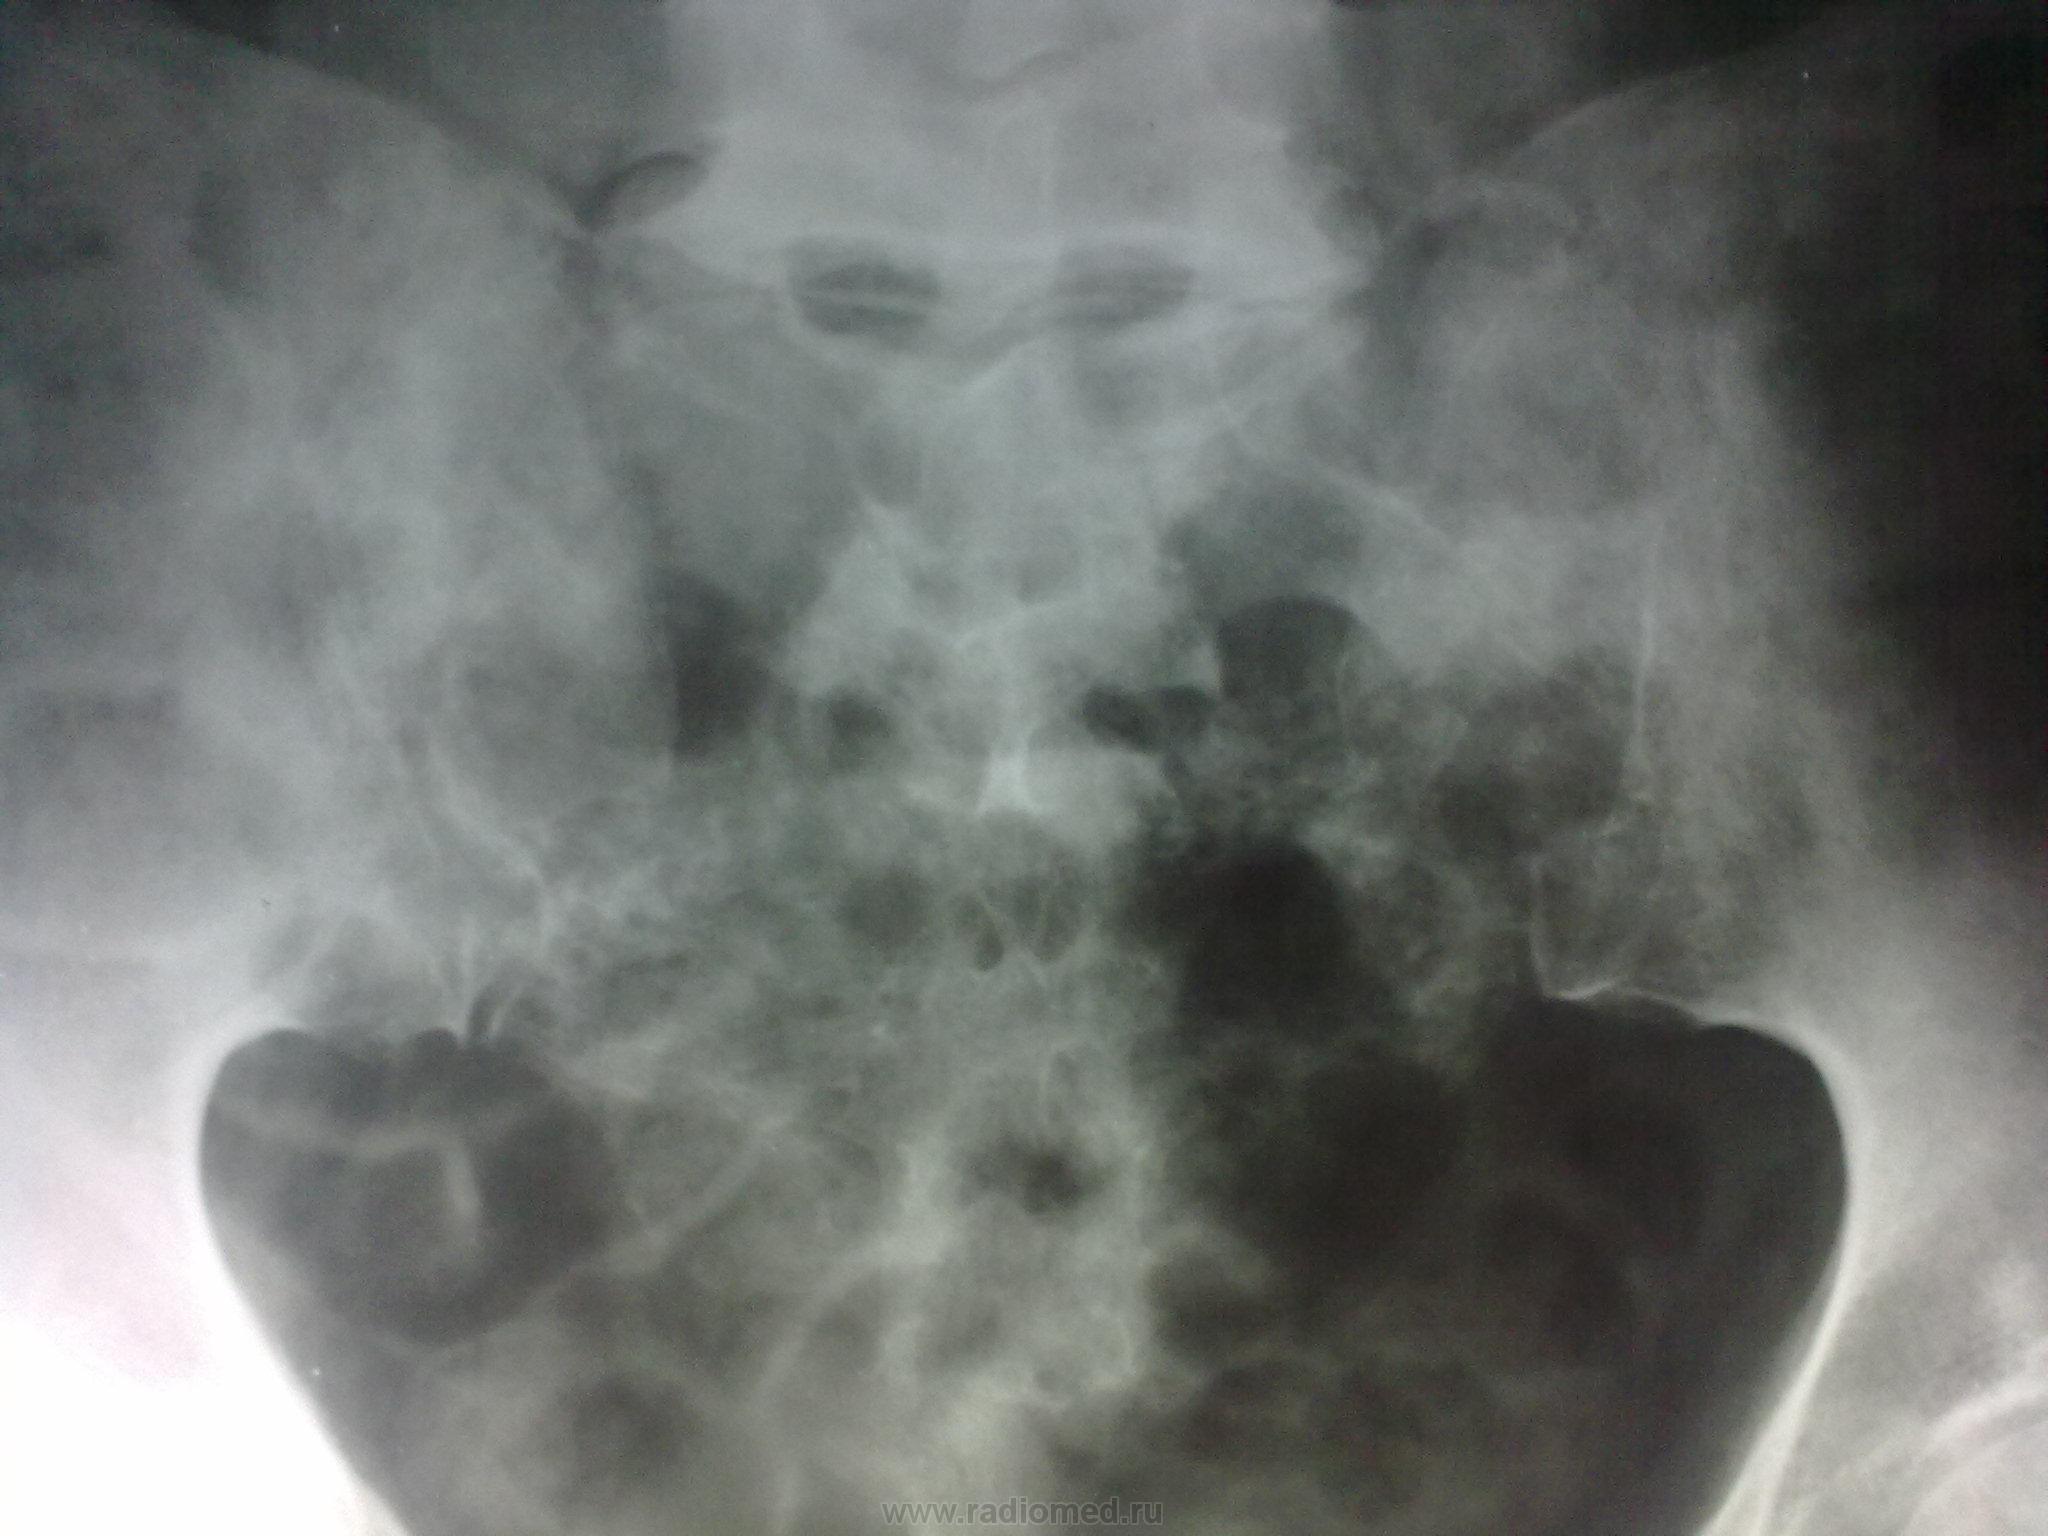

Пол пациента: Женский пол Тип патологии: Злокачественное новообразование Область исследования: Скелетно-мышечная система Методы исследования: Rg Рентгенограммы коллеги, врача-гинеколога, отказавшейся в свое время от мастэктомии по поводу злок. новообразования, лечившейся консервативными методами. https://radiomed.ru/sites/default/files/styles/case_slider_image/public/user/3055/samolechenie_raka_molochnoy_zhelezy_2.jpg?itok=h21nwmoF https://radiomed.ru/sites/default/files/styles/case_slider_image/public/user/3055/samolechenie_raka_molochnoy_zhelezy_3.jpg?itok=TTNqSoqp ID:9204 Вс, 21/11/2010 - 10:24 #1 Helios Не на сайте Был на сайте: 7 месяцев 2 недели назад Зарегистрирован: 06.08.2010 - 15:16 Публикации: 4417 No comments. Вс, 21/11/2010 - 15:09 #2 lupan Не на сайте Был на сайте: 6 лет 10 месяцев назад Зарегистрирован: 07.01.2010 - 17:17 Публикации: 1406 Что же. Сапожник без сапог. Великое преймущество врача заключается в том, что он не обязан следовать собственным советам. ( А. Кристи) Вс, 21/11/2010 - 20:21 #3 Катенёв Валенти... Не на сайте Был на сайте: 7 лет 1 неделя назад Зарегистрирован: 22.03.2008 - 22:15 Публикации: 54876 Обработанные снимки.Приложения: Пнд, 22/11/2010 - 20:18 #4 tatyana Не на сайте Был на сайте: 4 года 1 месяц назад Зарегистрирован: 24.06.2009 - 08:33 Публикации: 2090 Игорь иванович, а почему Вы так назвали тему? Вы считаете, что мастэктомия гарантирует от мтс в кости? Это не так. "самоуверенность дилетантов - предмет зависти профессионалов" Пнд, 22/11/2010 - 21:36 #5 Игорь Иванович Не на сайте Был на сайте: 3 года 9 месяцев назад Зарегистрирован: 23.01.2010 - 14:56 Публикации: 3695 tatyana wrote: Игорь иванович, а почему Вы так назвали тему? Вы считаете, что мастэктомия гарантирует от мтс в кости? Это не так. Да нет, я так не считаю, слишком много видел. А назвал, потому что доктор!!! Ауто знала, ауто отказалась от операции. Пнд, 22/11/2010 - 22:33 #6 tatyana Не на сайте Был на сайте: 4 года 1 месяц назад Зарегистрирован: 24.06.2009 - 08:33 Публикации: 2090 Почему же тогда - беспечность? может наоборот - информированность? "самоуверенность дилетантов - предмет зависти профессионалов"

Обработанные снимки.